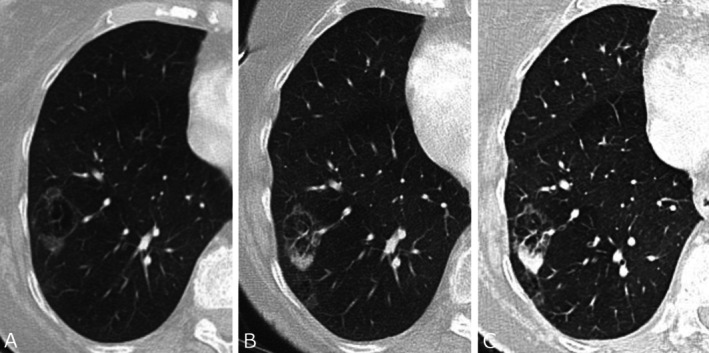

越来越多的肺癌筛查项目的采用和成像技术的进步显著增加了肺结节的检测,无论是偶然的还是通过筛查。本文件为临床医生提供了一个全面的指南,以解决管理不确定肺结节(ipn)的复杂性,强调以人为本和多学科的护理。ipn根据大小和形态进行分类,并有恶性肿瘤风险分层、诊断评估和随访的具体指南。专门的肺结节评估小组(LNETs)和结节多学科会议(MDMs)在确保指南遵守、简化诊断途径、减少不必要的调查和改善结果方面发挥着关键作用。结构化IPN项目在早期肺癌检测、改善早期肺癌检测和减少治疗启动延迟方面已经证明了益处。有效的管理策略包括使用标准化的报告模板,利用经过验证的风险模型,如PanCan恶性肿瘤风险模型和议定的ipn后续协议。本文档强调了获取先前成像以评估生长和计算计算机断层扫描(CT)扫描之间的技术差异的重要性。任何被认为正在生长的结节都需要在结节MDM上进行讨论,并决定酌情进行组织活检。基于结节特征和风险概况,结节MDM有助于优化最安全、最有效的活检技术。通过整合多学科专业知识和坚持以证据为基础的协议,服务可以改善ipn的及时诊断和管理,最大限度地减少过度调查,减少过度诊断的机会,并最终提高患者的预后和肺癌生存率。

The increasing adoption of lung cancer screening programs and advancements in imaging technologies has significantly increased the detection of pulmonary nodules, both incidentally and through screening. This document provides a comprehensive guide for clinicians to address the complexities of managing indeterminate pulmonary nodules (IPNs), emphasising person-centred and multidisciplinary care. IPNs are categorised based on size and morphology, with specific guidelines for malignancy risk stratification, diagnostic evaluation, and follow-up. Dedicated lung nodule evaluation teams (LNETs) and nodule multidisciplinary meetings (MDMs) play a critical role in ensuring guideline adherence, streamlining the diagnostic pathway, reducing unnecessary investigations, and improving outcomes. Structured IPN programs have demonstrated benefits in early lung cancer detection, improved detection of early-stage lung cancer, and reduced delays to treatment initiation. Effective management strategies include use of standardised reporting templates, utilising validated risk models such as the PanCan malignancy risk model and agreed protocols for follow up of IPNs. This document highlights the importance of accessing prior imaging to assess for growth and accounting for technical differences between computed tomography (CT) scans. Any nodule considered to be growing requires discussion at a nodule MDM with decision to act for tissue biopsy as appropriate. A nodule MDM will assist in optimising the safest and most efficient biopsy techniques based on nodule characteristics and risk profile. By integrating multidisciplinary expertise and adhering to evidence-based protocols, services can improve the timely diagnosis and management of IPNs, minimise over-investigation, reduce chance of overdiagnosis and ultimately enhance patient outcomes and lung cancer survival.